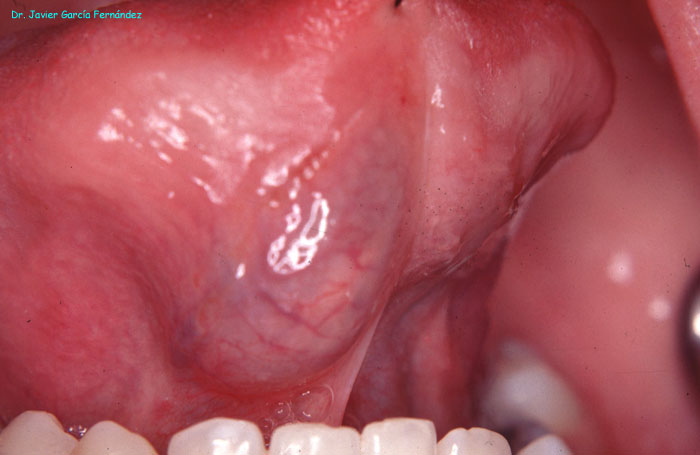

Atlas of Surgical Techniques in Periodontics. Chapter I. Diagnostic of Peridontal Diseases. Classification. Atlas de Técnicas Quirúrgicas en Periodoncia. Cap. I. Exploración y Diagnóstico. Atlas de Técnicas Quirúrgicas en Periodoncia

image136